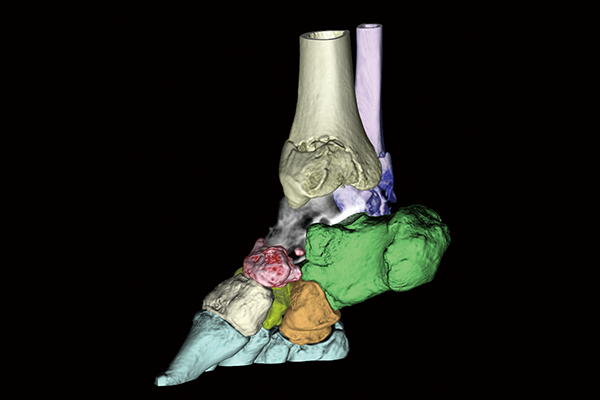

The image processing technology that Fujifilm has cultivated to date is also installed in the Operating Console of our CT system, enhancing the analysis functions. By simultaneously storing the reconstructed images in the Operating Console of our CT system and transferring them in parallel to SYNAPSE 3D, the waiting time from the end of the scan to the start of analysis can be shortened.

SYNAPSE 3D’s advanced image analysis technology aids clinical interpretation, reporting, and treatment planning. Especially,

automatic organ segmentation technology enables fast and effective workflow, powered by REiLI, FUJIFILM's AI brand. With

a series of high-tech applications developed in collaboration with clinical specialists, SYNAPSE 3D quickly and accurately

delivers imaging result that promotes effective care collaboration.

Bones are extracted or removed with one click based on the CT value and the shape of the region of interest recognized by REiLI technology.

Carpal bones removal

Lower extremity bones removal

Orthopedics